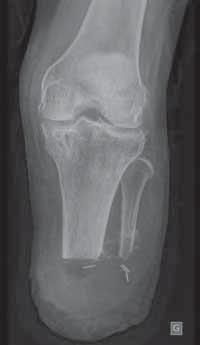

dalszej podudzia